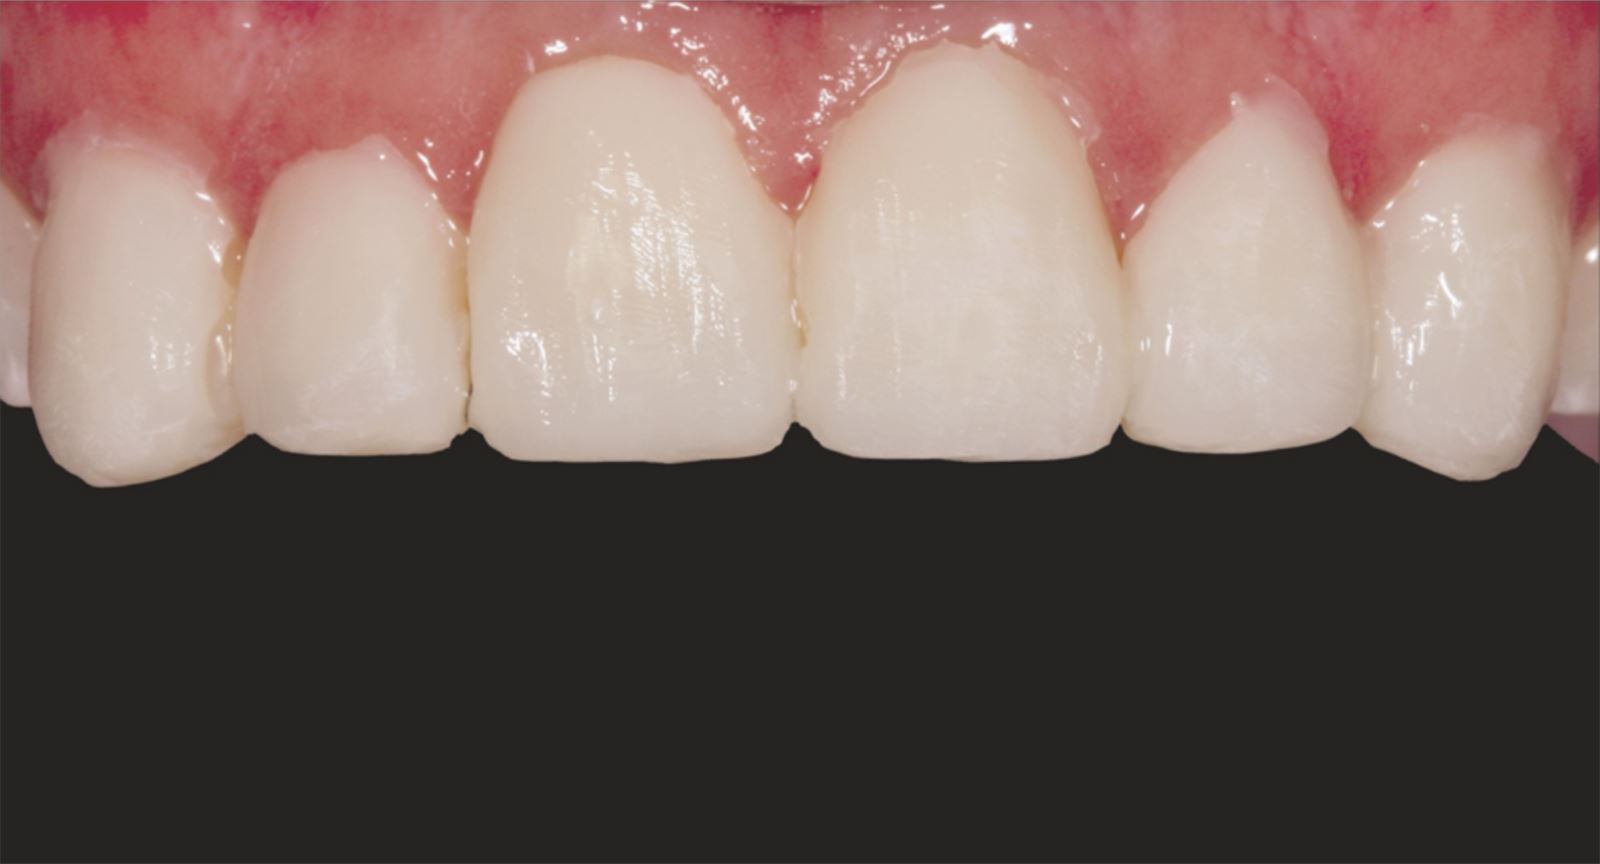

Mladá žena ve věku kolem 20 let, kterou trápila diskolorace horních frontálních zubů po dřívějším traumatu, vyhledala ošetření u Dr. Jaleeny Fischer-Jessop, DDS, MBA. Hledala řešení, které by obnovilo její úsměv. Pacientka byla ošetřena konzervativní a cenově dostupnou metodou: kompozitními fazetami bez preparace, přímým bondingem. Dr. Fischer-Jessop zvolila tento postup k překrytí diskolorace a sjednocení horních zubů s dolními frontálními – bez nutnosti invazivnějších výkonů, jako jsou implantáty, nebo nákladných laboratorně zhotovovaných fazet. Pro zesvětlení zubů byly vybrány odstíny B1D a Enamel White (EW) a odstín Universal Body (UB) kompozitu Transcend™ byl použit k přirozenému splynutí okraje v cervikálních oblastech.

Kompozit Transcend v odstínu B1D byl aplikován od dvou třetin výšky korunky od incisální hrany směrem k cervikální oblasti, kde se postupně ztenčoval. Odstín Universal Body (UB) byl nanesen v cervikálním třetině, závěrečné vrstvy tvořil Enamel White (EW) a malé množství UB v marginální oblasti pro přirozené splynutí.

Tento postup úspěšně vyřešil estetické obavy pacientky překrytím diskolorace horních frontálních zubů a dosažením přirozeného, vyváženého vzhledu ve vztahu k dolním frontám. Použití kompozitních fazet bez preparace poskytlo konzervativní, vysoce efektivní řešení, které respektovalo finanční možnosti pacientky a její požadavek na minimálně invazivní přístup.